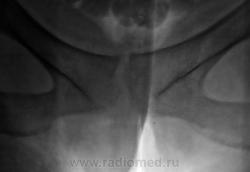

2. Лонное сочленение очевидно,подверглось значительному растяжению (имеется локальный вакуум-феномен слева), умеренно выраженые явления симфизита (опять же - постравматического).

1. По первым снимкам не отпускало впечатление о повреждении левого крестцово-подвздошного сочленения. После подготовки вроде-бы все нормально, но все равно что-то гложет.

2. А на боковой массе крестца справа разве не линия консолидирующегося перелома?

Возможно, перелом последнего копчикового тоже был?

Поздно заметил ветку.. увидел симфизит, перелом остистого L4, мазоль Co 5, и  конечно spina bifida S1 ))) глянуть бы межпозвоночные..